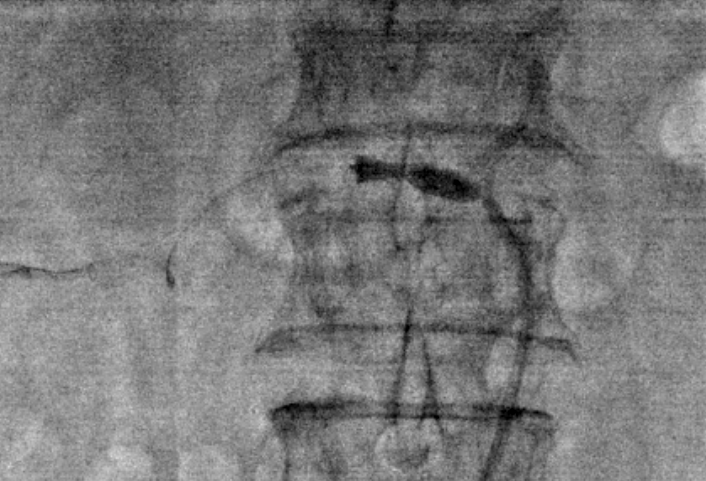

全身肝素化,7F RDC配合4F Sim1导管选入右肾动脉,(4mm-20mm)Aviator Plus球囊预扩,植入(6mm-18mm)Palmaz Blue支架。

7F RDC配合4F Sim1导管选入左肾动脉,(4mm-20mm)Aviator Plus球囊尝试送入左肾动脉困难,更换(2mm-15mm)Gateway球囊后成功送入左肾动脉并完成预扩,植入(5mm-18mm)Palmaz Blue支架。

4、Palmaz Blue支架具有显影性佳、短缩率低、低外径和柔顺性高等优点,直径范围在4-7mm,适用于肾动脉狭窄的介入治疗。Aviator Plus球囊是一款快速交换球囊,直径范围在4-7mm,可配合Palmaz Blue支架使用。